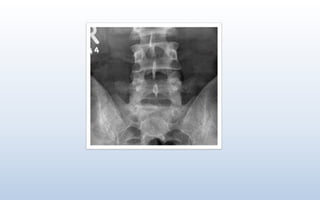

X-ray findings in the Sacroiliac Joint

Sacroilitis is usually the first manifestation and is symmetrical. It is the hallmark of

Ankylosing Spondylitis.

Sacroilitis is characterized by:

• Fuzziness of joint margin. Loss of sharp outline. Joint show irregularity & there is loss

of cortical margins.

• Erosions starting on the iliac side of the joint, causing pseudo-widening of the joint

space.

• Juxta-articular sclerosis

• Obliteration of Joint space

• Fusion of the sacroiliac joint ( Ankylosis )